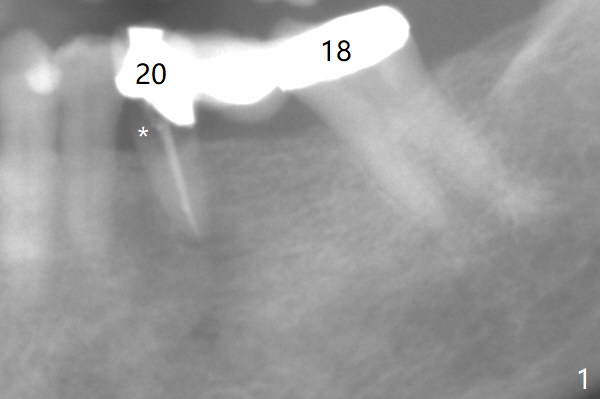

A 64-year-old woman has a lower left FPD (Fig.1) with the abutment at #20 having open margin (*). The tooth seems to be non-salvageable and to be replaced by an implant. There is ~ 6 mm native bone (Fig.2). Mesial osteotomy should be safer than orthodox one (Fig.3). To have the best reference, the FPD will be first sectioned between #19 and 20 (Fig.3 red line). Initial depth will be 18 mm (gingival level). An implant will be placed using the pontic at #19 and the tooth #21 for orientation guide. After placement of an abutment at #20 and use of gauze to seal the socket, the FPD will be sectioned between #18 and 19. It appears that the tooth #20 and probably #18 have fractured (Fig.4). Implants will be most likely placed at #18 and 20. The existing bridge will be used as a provisional.